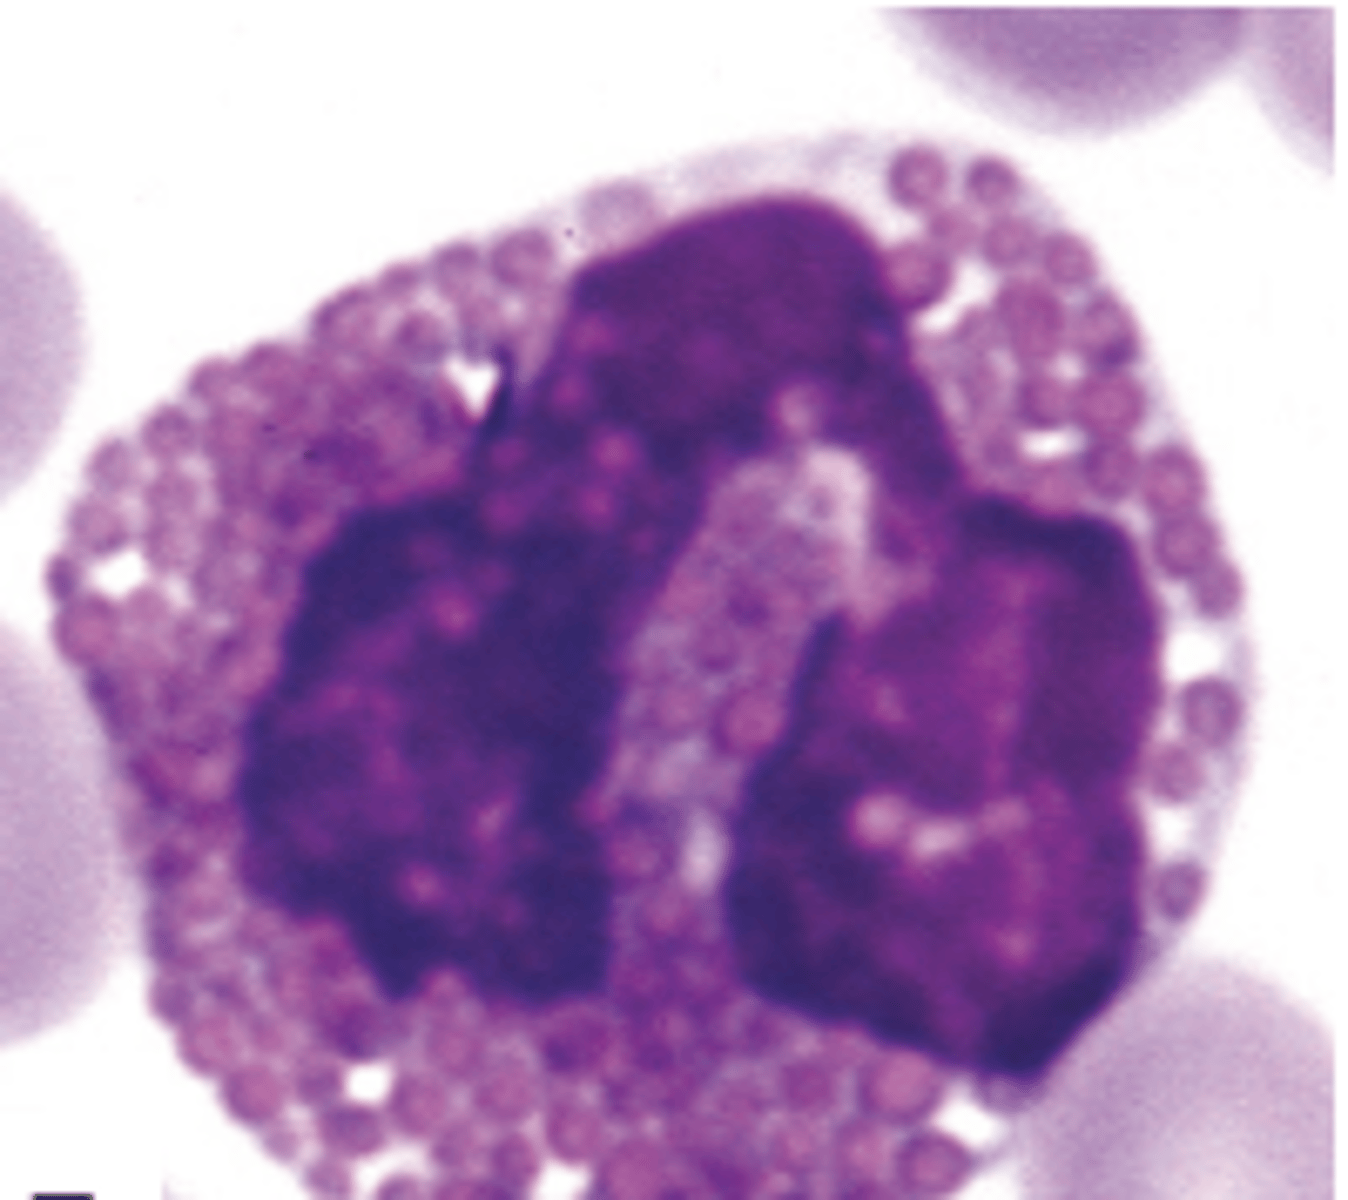

A Barr body or inactive X chromosome; implies that this sample is from a female patient

The arrow in the image is pointing to what structure? What does this imply?